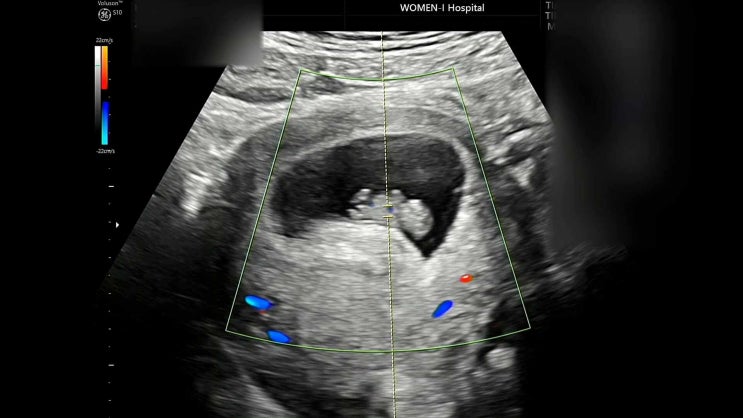

[pregnancy.8]임신 초기에서 점점 안정이 되어가는13주14주이야기(대구여성아이병원,1차입체초음파,임산부왁싱,보건소임산부교실,뚱채김밥,수박,신마산식당,ici에타,최가네케크)

안녕하세요~ 보통은 임신 초기와 안정기 주수가 12주라고 이야기하지만 저는 출혈이 있고 그래서 선생님이 ...